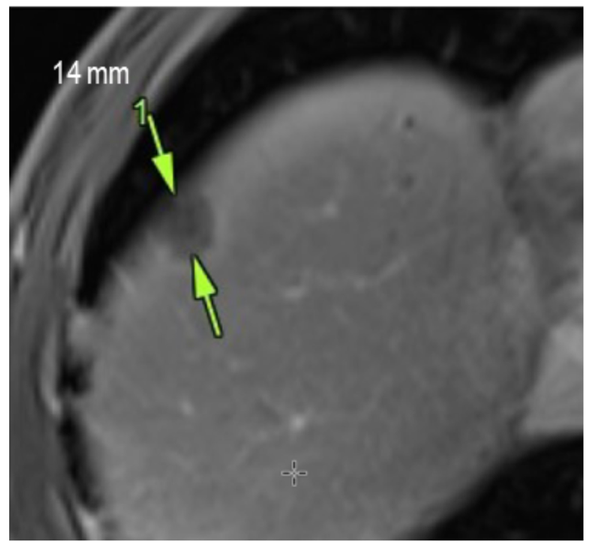

We are proud to share that our latest case report has been published in Frontiers in Oncology ! In this study, we describe a patient with advanced-stage prostate cancer and extensive bone metastases who responded positively to our personalized peptide-based immunization therapy (BITAP). Administered as a monotherapy, BITAP was associated with regression of both metastatic and primary tumor lesions, stabilization of PSA levels, and only mild, short-term side effects. This case underscores the potential of personalized peptide immunization as a promising therapeutic approach for treatment-resistant prostate cancer. We are deeply grateful to everyone who helped make this work possible. Read the full article here .